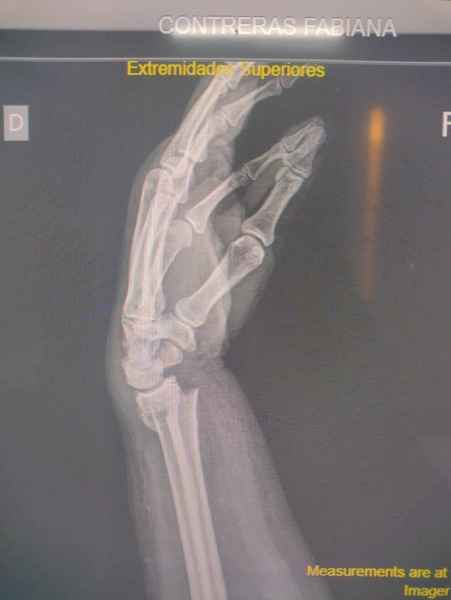

En la Artritis Reumatoidea el compromiso de las articulaciones interfalángicas proximales, metacarpofalángicas y de la muñeca estan generalemente afectadas simetricamente, lo que la distingue de la Artrosis, en la cual el compromiso se observa predominantemente en las articulaciones interfalángicas distales.

Cambios agudos como ser dolor o edema, pueden ser indicio de Artritis aguda o ataque de Gota aguda, los cambios crónicos tienden a modificar la estructura y anatomía normal de las manos como ser los dedos en cuello de cisne, mano en ventarrón, característicos de la Artritis, mientras que en la Gota crónica se observan tofos gotosos con deformidad de grandes articulaciones de la mano.

La exploración de la sensibilidad y motricidad de la mano son de utilidad en el exámen neurológico cuando se sospecha lesión de algunos de los nervios terminales del plexo braquial, dando signos característicos como son la mano en garra en la parálisis cubital, mano del mono, debido a una atrofia de la eminencia tenar debido a lesion del nervio mediano y mano péndula en la parálisis del radial.